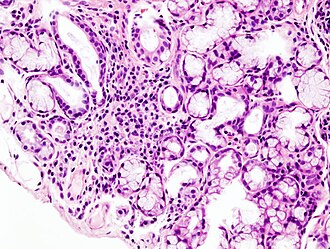

Histopatološka slika žarišne limfoidne infiltracije male žlijezde slinovnice povezna sa Sjögrenovim sindromom.